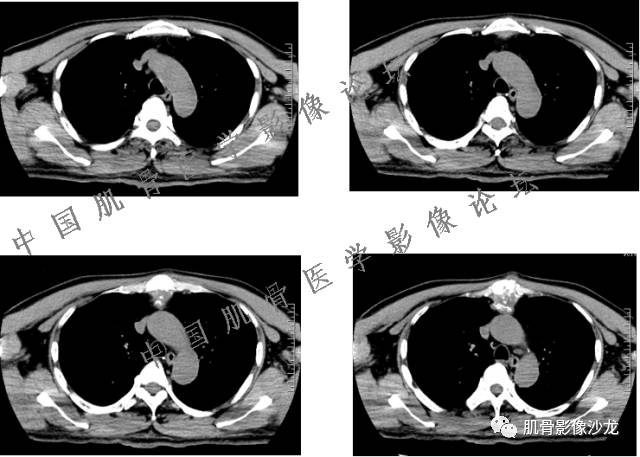

1、软骨肉瘤可以有膨胀性骨质破坏(病例3,4),可以有溶骨性骨质破坏(病例2),局部皮质因为破坏变薄,中断 ;

2、软骨基质T2WI高信号,软骨小叶分叶状,也就会出现高老师提到的骨内膜扇贝形压迹。一般认为骨内膜扇贝形压迹超过骨皮质厚度的2/3是软骨肉瘤在长管状骨的特征性表现。如上图。3、软组织肿块或肿胀;

4、 钙化,环形,弓形,边缘模糊 ;

5、增强后进行性延迟,不均匀分割状强化, 会强化的纤维间隔,软骨小叶不会强化,关于老师们说到的钙化,软骨肉瘤不一定会有钙化 。

雪舞 :1、骨恶性肿瘤的发病率排名:多发骨髓瘤、骨肉瘤和软骨肉瘤

2、软骨肉瘤的发病部位排名:最好发部位为髂骨,其次股骨、肱骨和脊柱。